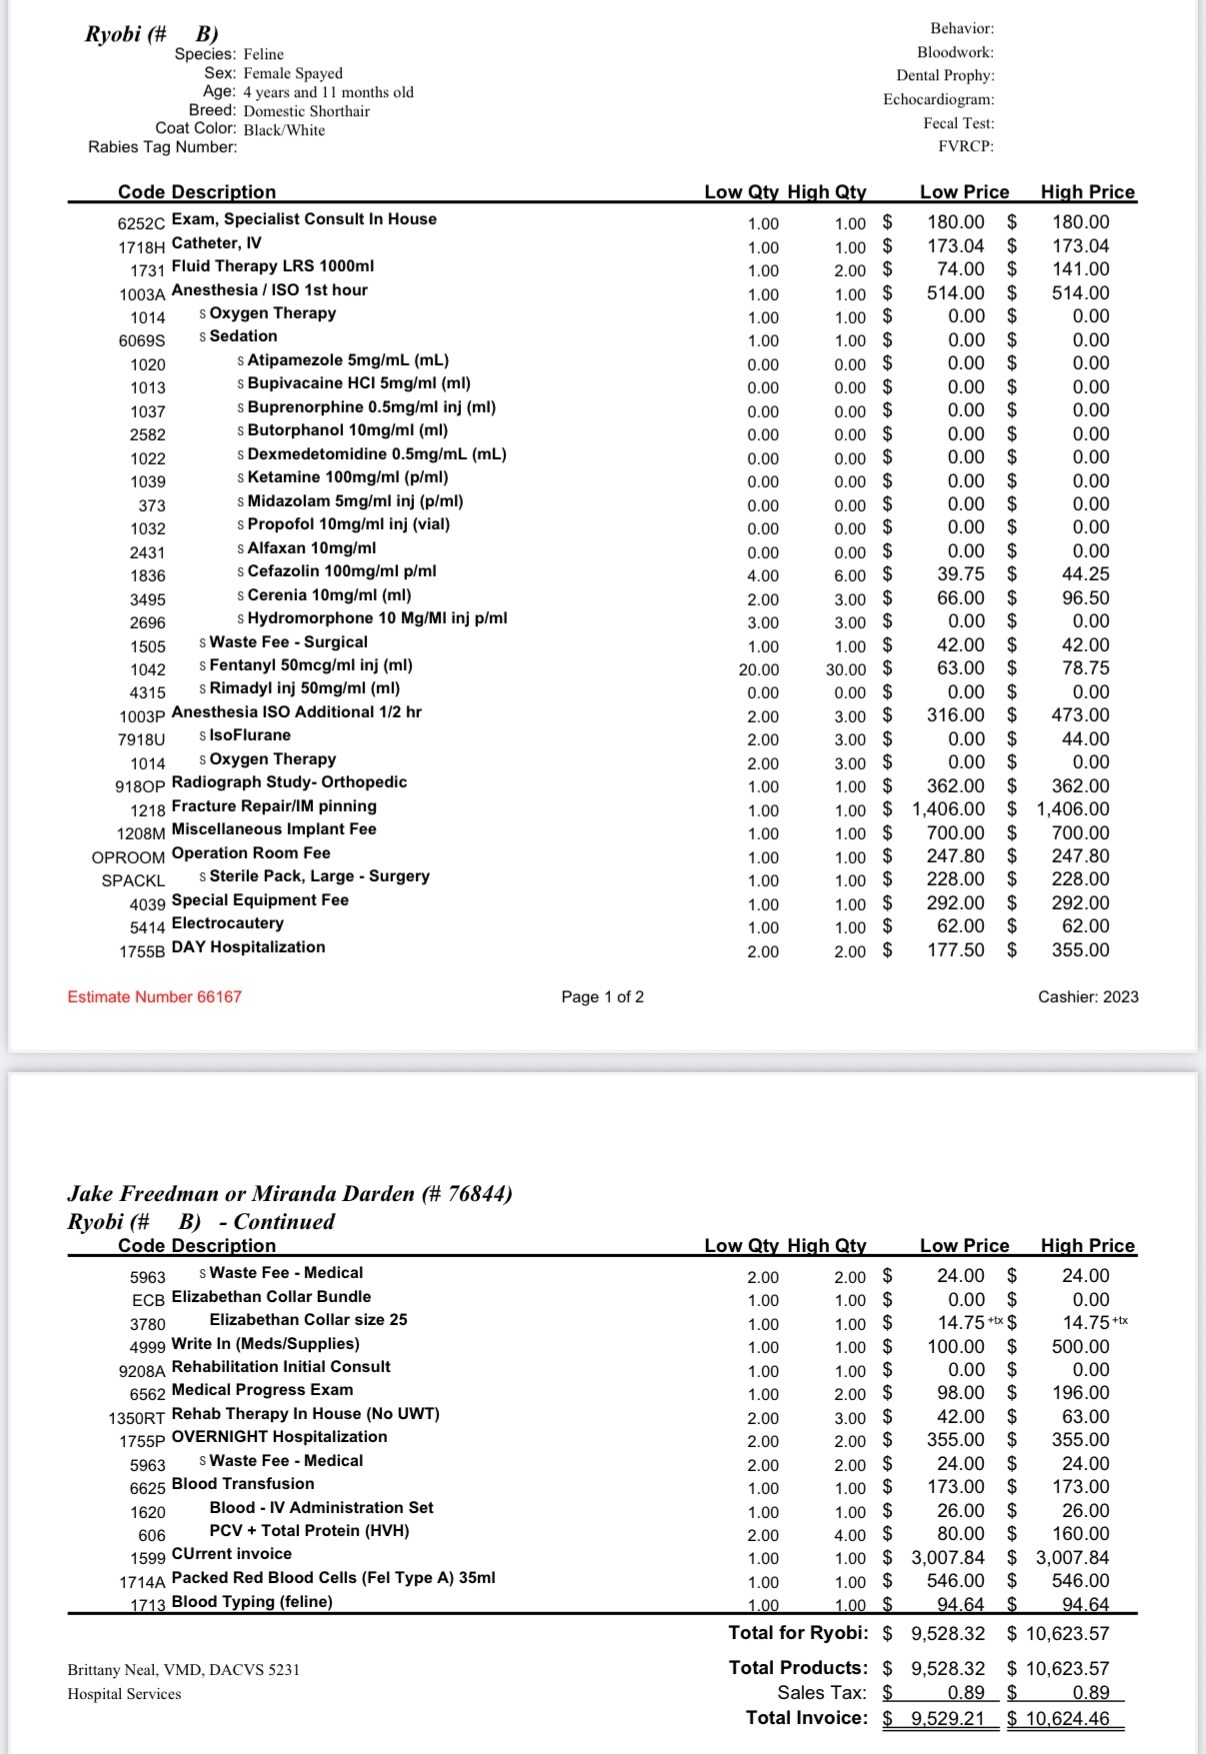

On Sunday morning, when she didn’t show up for breakfast, we knew something was wrong. We soon discovered she had been hit by a driver and left in pain, unable to move. Thankfully, we found her in time to get her the urgent care she needed. Ryobi suffered multiple pelvic fractures and now faces surgery to walk again and return to a normal life.

The cost of her treatment is overwhelming, but we couldn’t stomach the idea of putting her down when she still has such a strong chance at a pain free future. Every donation, no matter the size, will go directly toward her medical expenses and recovery.